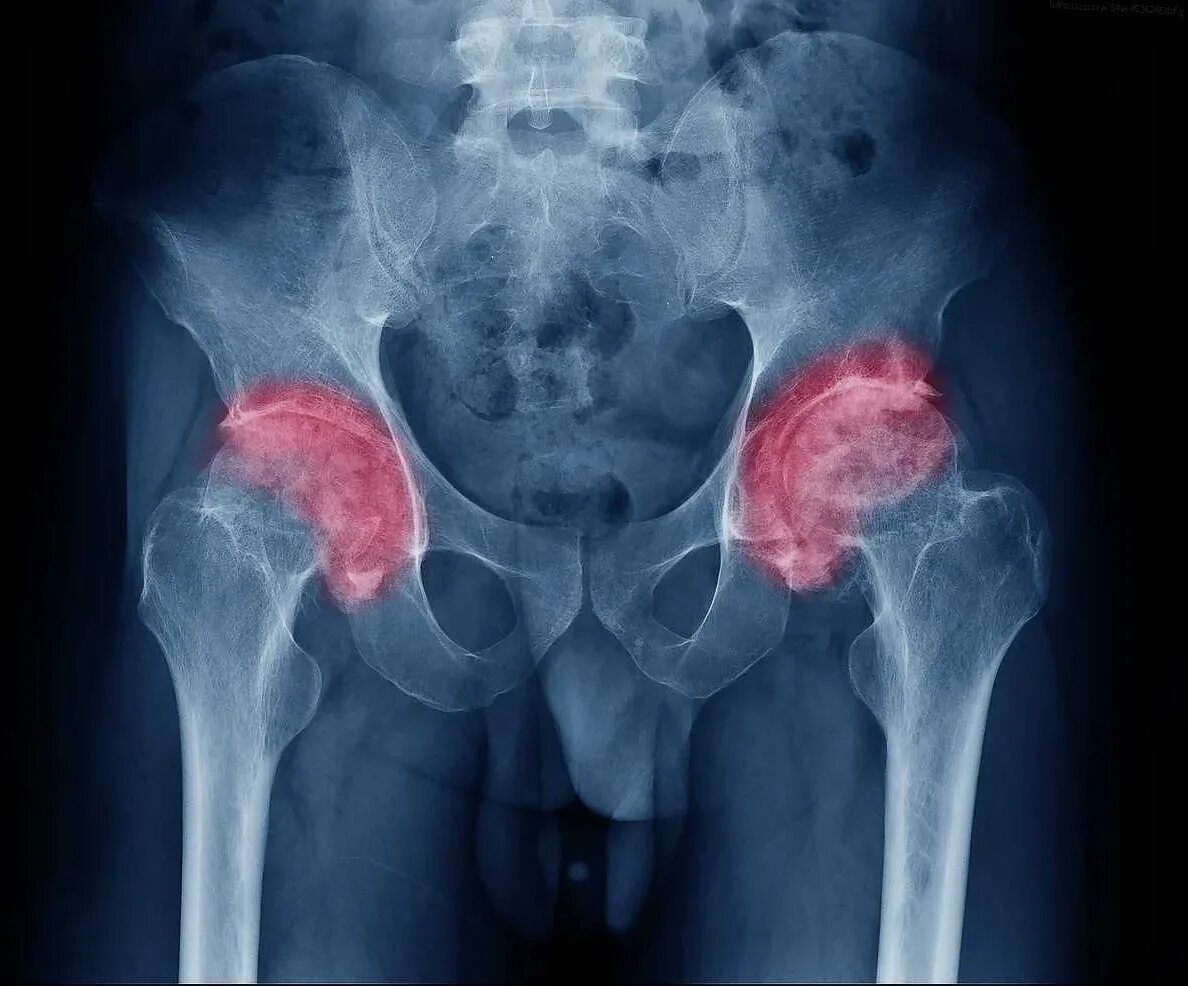

Тазобедренный сустав симптомы болезни